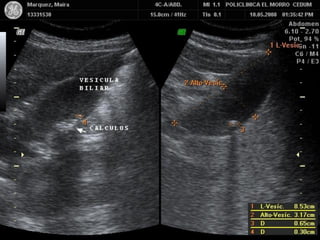

PATOLOGIA BILIAR

LITIASIS VESICULAR